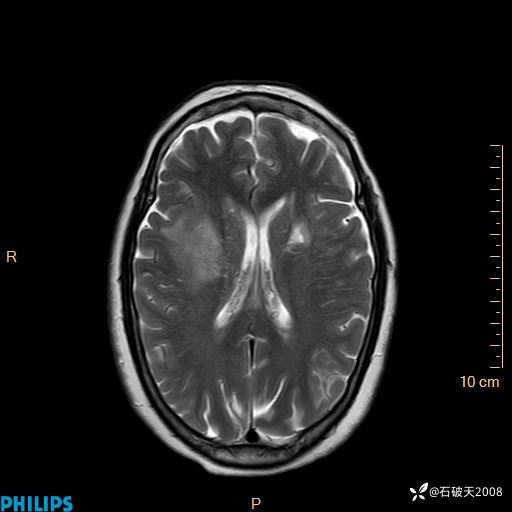

2020.11.14MR

T2